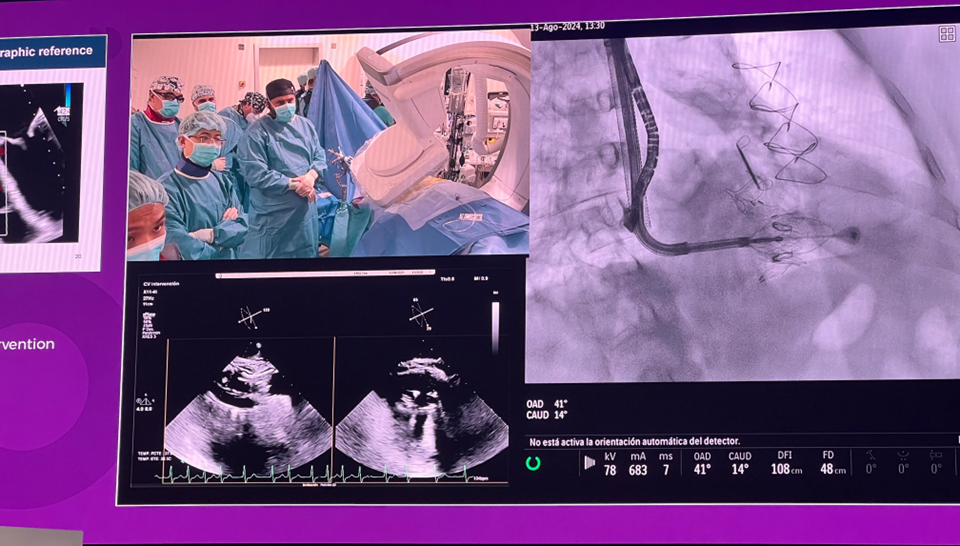

隨后由來自西班牙維哥-阿爾瓦羅昆奎羅醫(yī)院(Hospital Álvaro Cunqueiro, Vigo, Spain)的 Rodrigo Estevez-Loureiro 教授在大會主會場的經導管介入瓣膜新技術環(huán)節(jié),帶來了一例 LuX-Valve Plus 手術錄播,對手術植入的步驟和關鍵要點進行了詳細深入的介紹。同時,臺上的多位討論嘉賓也結合他們的 LuX-Valve Plus 手術經驗進行了深入的探討。來自香港瑪麗皇后醫(yī)院(Queen Mary Hospital, Hong Kong, China)的 Simon Lam 教授分享了 LuX-Valve Plus 在術前有起搏導線病人中的植入經驗,來自巴西圣保羅(Rede D'Or São Luiz, São Paulo, Brazil)的 Vinicius Esteves 教授補充了 LuX-Valve Plus 獨特的非徑向支撐力設計,能夠實現非常低的術后起搏器植入率,來自法國波爾多大學醫(yī)院(CHU de Bordeaux, Bordeaux, France)的 Lionel Leroux 教授則分享了其在LuX-Valve Plus歐洲臨床試驗過程中,對于大尺寸瓣環(huán)植入的優(yōu)異結果。